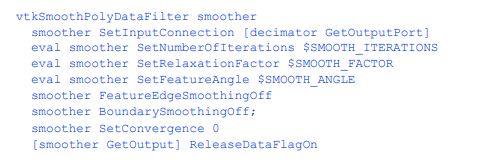

平滑三角形顶点

该过滤器使用在第350页的“网格平滑”中描述的拉普拉斯平滑来调整三角形顶点作为相邻顶点的“平均值”。通常,移动将小于一个体素。

452应用程序

当然,我们已经用高斯核平滑了图像数据,所以这一步可能不会有太大的改进;然而,严重抽取的模型有时可以通过额外的多边形平滑来改进。